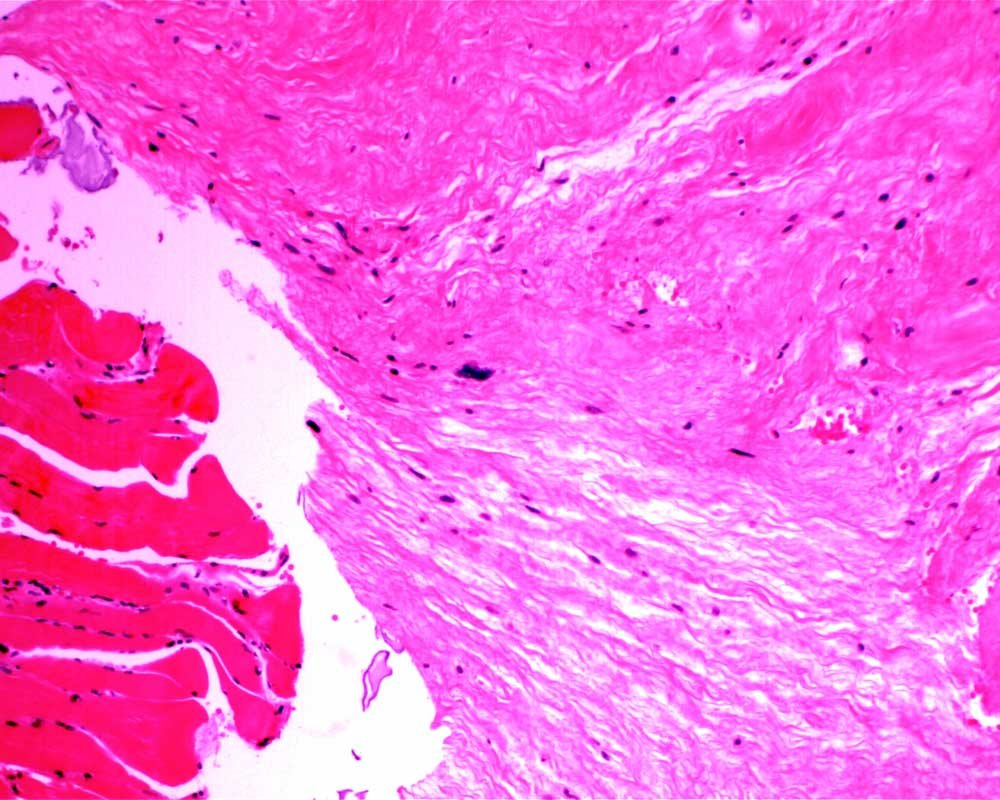

Case: ThighMass2

Final Diagnosis: